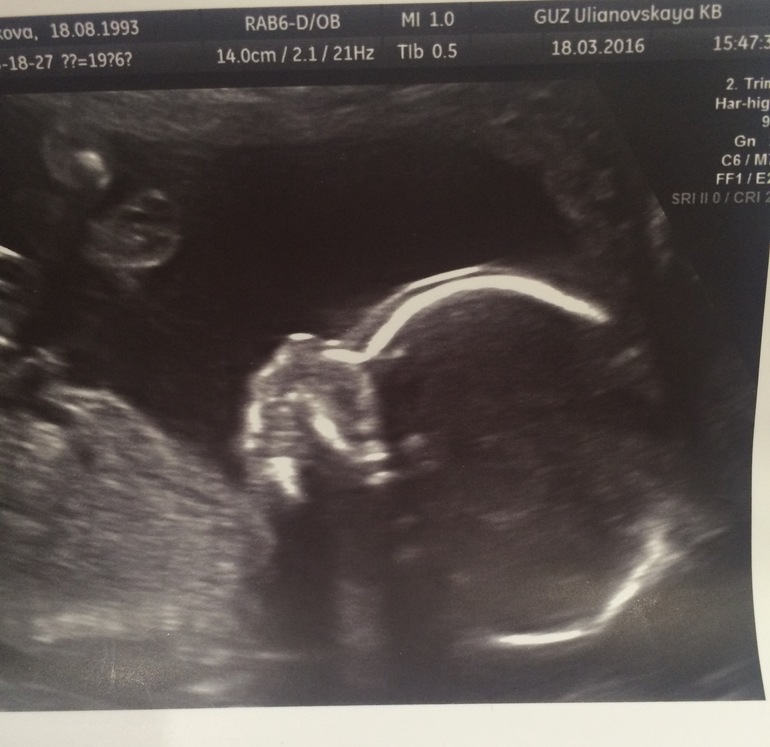

2 скрининг и экватор)) ❤️❤️❤️

Слава богу все хорошо))🐥 развиваемся в срок)) подтвердили МАЛЬЧИКА))😍😍😍 показали писюльку - её точно уже не с чем не перепутаешь))👶🏼❤️ Малыш активничал, стучал ногами, трогал свою свою шею, моську)) правда сначала не хотел поворачиваться и показывать лицо, но все таки повернулся котенок))💕😻 ножки длинные, стопа большая, на руках по 5 пальчиков☺️☺️☺️ Весим 290 грамм, носик 6 мм, ЧСС 151..)) единственное, что меня напрягло, это шейка 29,8мм и низкая плацентация.. Фото под кат..))